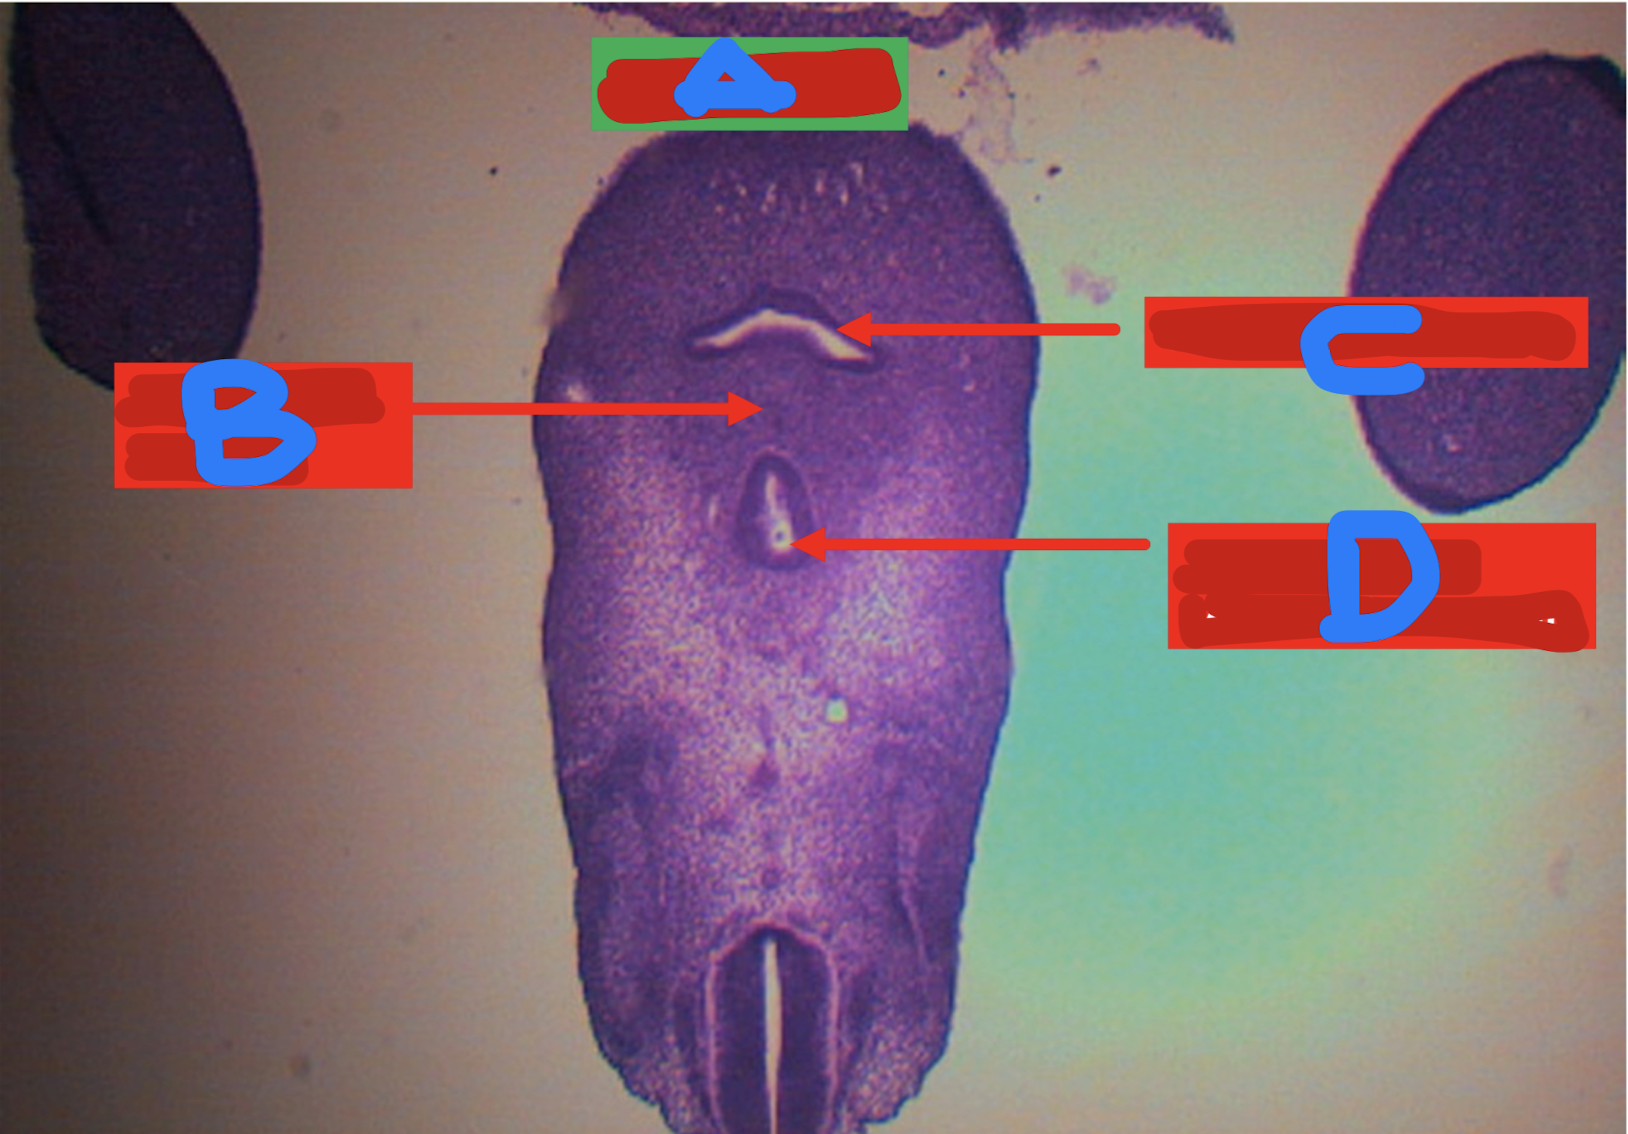

DUODENUM

Brunner’s gland or duodenal glands

secrete alkaline fluid composed of mucin as protection for acidic chyme from stomach

Identify the structure

A: mucosa

B: submucosa

C: tunica muscularis

D: tunica serosa/adventitia

E: intestinal glands

Arrow: Brunner’s gland